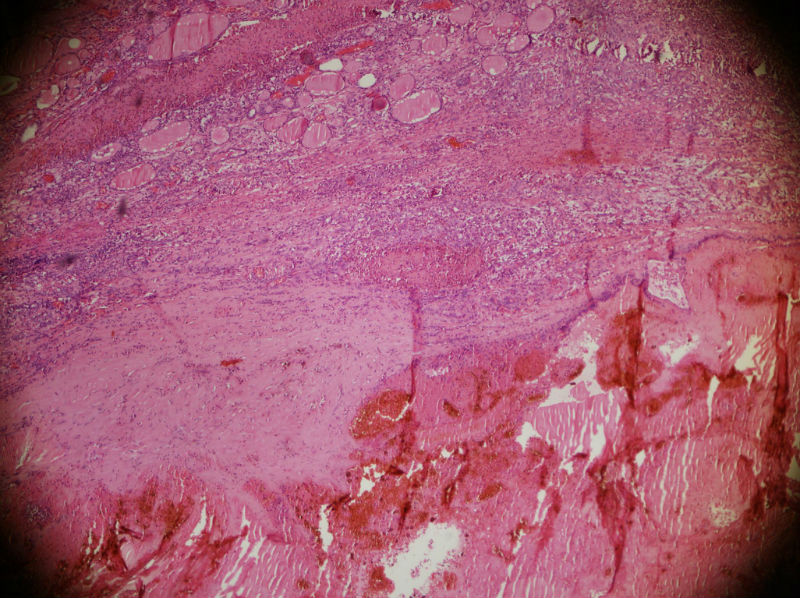

男,44,甲状腺囊肿.直径1.5公分,内流清亮液

• 甲状腺囊肿,请老师们指教图2

图2

结节性甲状腺肿伴出血、囊性变。囊肿边上的滤泡大小不一,纤维组织增生,还可见炎细胞浸润。